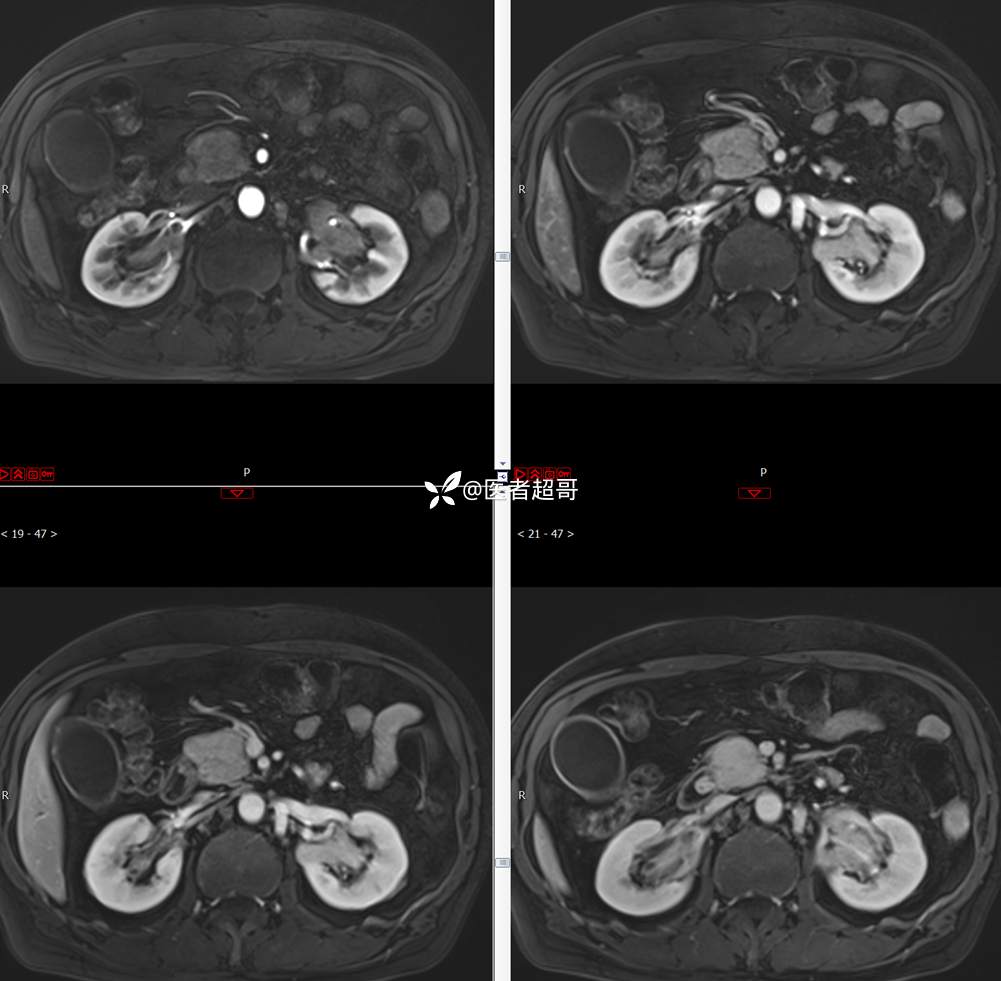

【影诊笔记772】腹痛就诊,发现肾脏病变,CT、MRI齐全,请高诊!

男,63岁 0200825 01

主 诉:间断腹痛15天

现病史:患者15天前无明显原因及诱因出现腹部疼痛不适,呈间断性钝痛,右下腹为著,无尿频、尿急、尿不尽,无发热、寒战,无腹胀。于市中心卫生院住院治疗,超声示:胰头低回声包块,胆系扩张,左肾囊肿,胆囊壁毛糙,胆囊内胆汁淤积。患者为求进一步诊治,遂以“肾盂肿瘤”收入院,患者自发病以来,神志清,精神可,饮食睡眠可,大便无明显异常,近期体重无明显增减。

既往史:既往体健